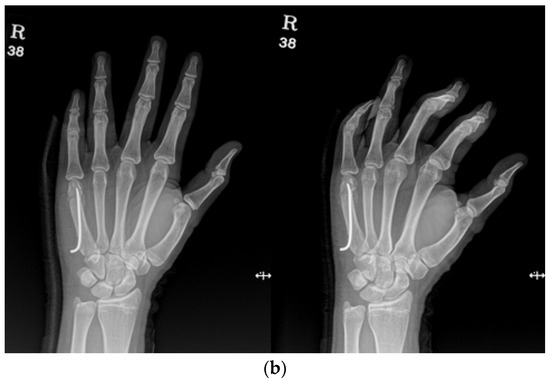

2.3. Surgical Technique